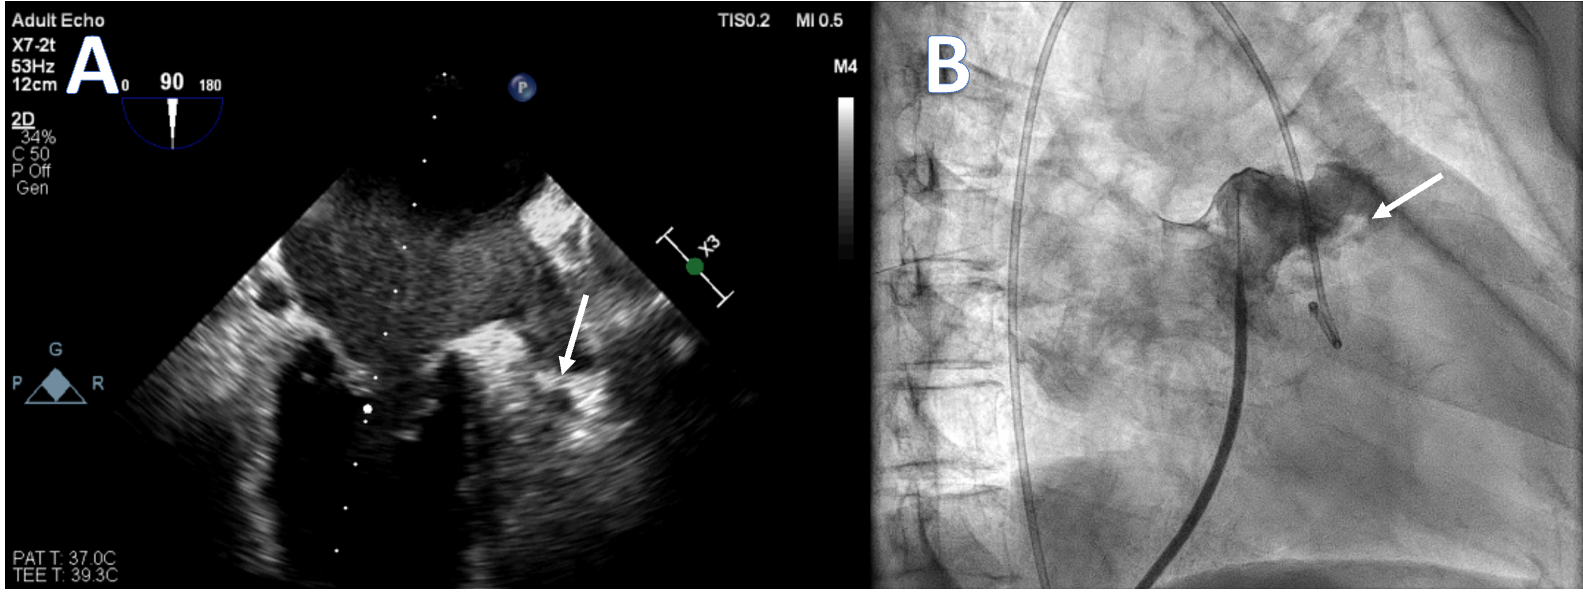

She was tachypneic upon examination, and diffuse wheezing was present on lung auscultation. The 12-lead electrocardiogram showed AF with a fast ventricle rate. Transthoracic echocardiography showed severe mitral restenosis (mitral valve area: 1.0 cm² [normal 4-6 cm2]) and reduced left ventricular function, likely due to persistent AF. Transesophageal echocardiography revealed spontaneous echo contrast in the left atrium and an organized thrombus in the left atrial appendage (LAA) tip (Manjunath Type 1a) (Figure A). In view of worsening symptoms, patient was initially stabilized and a redo PTMC was planned. During hospital stay, the warfarin was stopped and bridging with low-molecular-weight heparin was initiated.

After septal puncture, intraprocedural intravenous unfractionated heparin was given. The LA angiography demonstrated a dilated and fibrillating appendage with a "quivering" motion. A distinct area of haziness and a contrast-unfilled defect were visualized at the appendage tip (Figure B, Video). The PTMC was done with utmost care to prevent the movement of the balloon to the LAA appendage, and the mitral valve area increased to 1.8 cm².